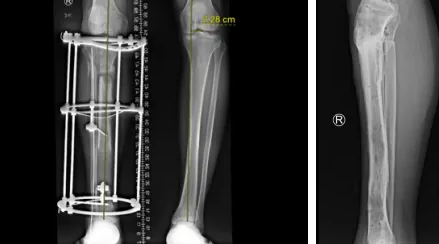

小张一场意外车祸导致小腿胫骨粉碎性骨折,在必威官方首页官网betway进行了骨延长手术,得知曹广超主任来看望他后,早早来到门口等待。

“当时医院都要截肢了,多亏转到了sararz,保住了这条腿,现在好的很,开车带孩子去云南玩,这要截肢了哪敢想。”

胫骨粉碎性骨折,伴有腓总神经损伤

骨延长术后